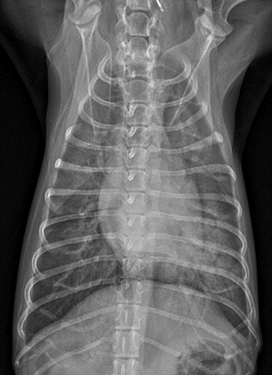

아래는 아이의 엑스레이 사진입니다.

검게 보여야 할 폐의 부분이 하얗게 보입니다, 더하여 방사선상 심장의 크기도 커 보입니다.

그렇습니다. 심장병에 의한 폐부종입니다.